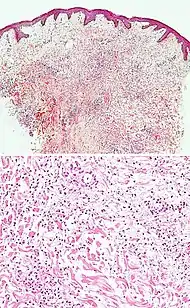

Interface dermatitis with vacuolar change

| Generally/Not otherwise specified | Typical findings, called "vacuolar interface dermatitis":[6]

|

An interface dermatitis with vacuolar alteration, not otherwise specified, may be caused by viral exanthems, phototoxic dermatitis, acute radiation dermatitis, erythema dyschromicum perstans, lupus erythematosus and dermatomyositis.[2]